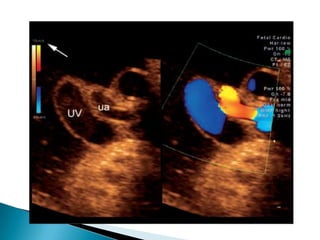

   Characteristic umbilical artery waveforms

have also been correlated to various degrees

of fetal hypoxemia and acidemia.

   Absent end-diastolic frequencies

◦ 75% of the placental vascular bed has been

obliterated

◦ 85% chance that the fetus will be hypoxemic and

a 50% chance that it will also be acidemic.

   Reversed end-diastolic frequencies

◦ ten-fold increase in perinatal mortality